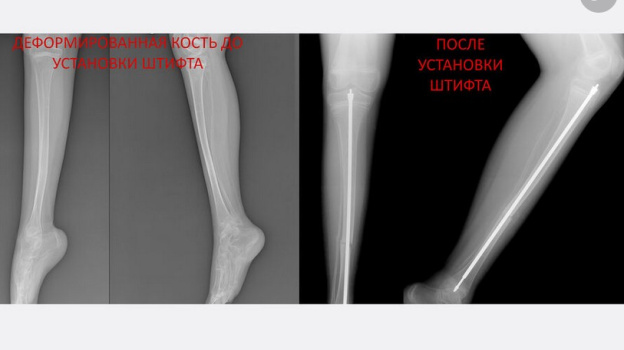

Врачи спасли самарского мальчика с "хрустальными" костями